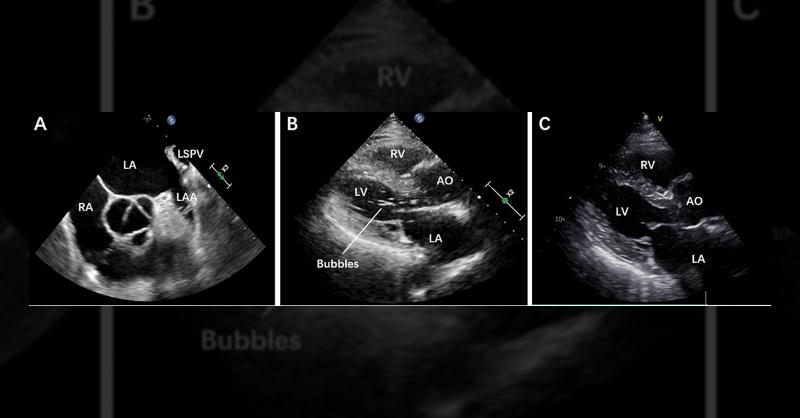

A 77-year-old man presented to our hospital with persistent nonvalvular atrial fibrillation (AF) spanning 6 years, evident through an irregular heartbeat and confirmed by electrocardiogram. Physical examination indicated AF, corroborated by TTE revealing left and right atrial enlargement alongside preserved LVEF (58%). Despite a CHA2DS2-VASc score